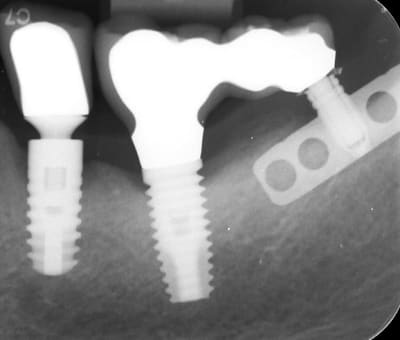

Je fait encore appel à votre expertise pour connaitre les marques des implants piliers de bridge (hormis l'implant Ankylos). En effet, la vis de l'implant mésial du bridge s'est fracturée me semble être un Branemark (posé il y a 20 ans). Il y a en pièce jointe deux photos de la vis fracturée.

Pour l'implant lame en distal ressemble à une lame de Linkow mais la présence d'un pas de vis interne ne semble pas correspondre à cette marque d'implant.

Oh put.. celui-ci, c’est un collector

Ça mériterait une petite radio bien centrée sur l’implant pour que je puisse le mettre dans « histoire de l’implantologie » d’Eugenol ...

j’ai lu dans un numéro du « fil dentaire » que quand il y a un pas de vis à l’interieur dans un implant lame c’ était Poulmaire qui l’avait inventé

Il y a presque plus de perte d’os sur l’Ankylos que sur le branemark ........ l’Ankylos ayant été posé plus récemment en plus...

sauf erreur je pense plutôt à une lame TBR tournevis plat possible (ou bien carré mais plus dur à trouver ) le pas de vis est le même à priori que les Anthofit d'Anthogyr année 86/87

Pour l'implant du milieu, pouvez-vous me confirmer que c'est un Branemark.

oui, l'implant du milieu, c'est un Nobel branemark

je reviens vers vous pour la marque de l'implant du milieu.

La commerciale de Nobel ne reconnait pas la tête de vis (conf.photos du premier post.).

Serait-ce un 3I par hasard?

fort possible que çà soit un 3i pour ton cas clinique...faut dire que les différences radiologiques avec les Nobel sont très faibles donc on peut se tromper facilement...

ce qui m'avait fait dire que c'était un Nobel c'est que sur les 3i en général c'est des vis en or...mais bon si c'est un pilier et vis de marque "adaptable" qui est dessus...

http://whatimplantisthat.com/implant/osseotite-parallel-walled-5/

pour ton associé, je dirais que c'est plus un vieux steri-oss

Effectivement la vis semble être du Biomet 3i.

Il y a des vis en or mais aussi en titane.